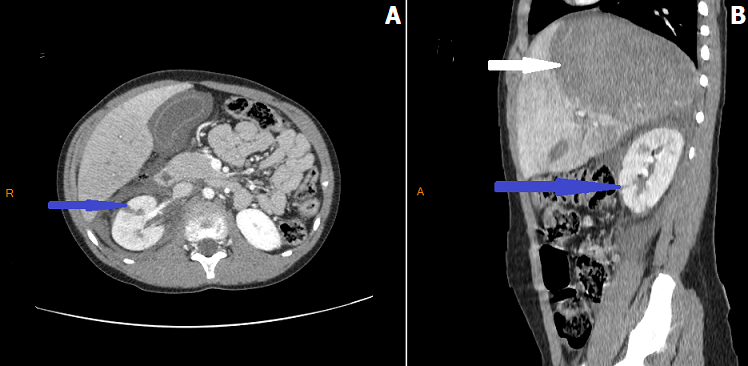

Figure 1: A) axial and B) sagittal abdominal contrast enhanced CT performed after a blunt abdominal trauma in an 11-years-old boy showing a parenchymal laceration of the right kidney (grade III of AAST Kidney Injury Scale) (blue arrows) associated with a voluminous hematoma of the liver (white arrow) after falling from standing height and who was managed conservatively